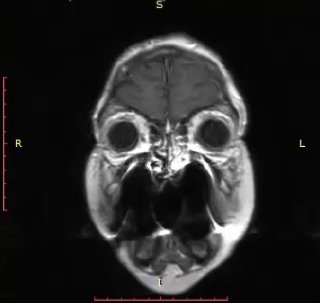

Рецидив метастаза рака молочной железы в зоне предыдущего удаления.

Выраженный перифокальный отёк мозга привёл к грубому гемипарезу.

После удаления очага неврологический дефицит практически полностью регрессировал.

Иногда даже при агрессивном течении заболевания вмешательство даёт пациенту не просто время, а качество жизни. На видео - МРТ до и после удаления.